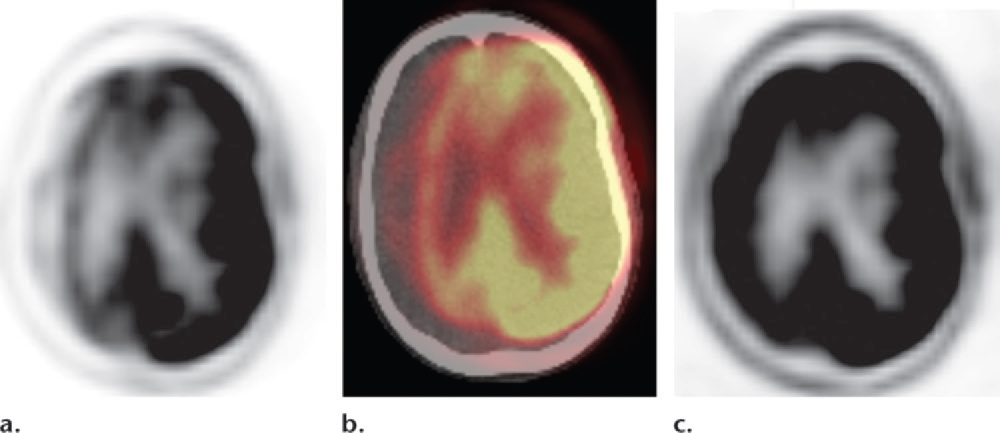

- movimento del paziente: un disallineamento tra le immagini PET e la TC utilizzata per la correzione dell’attenuazione può creare aree di apparente ipometabolismo (artefatto da errata sottrazione, o oversubtraction artifact). Questo artefatto potrebbe non essere evidente analizzando le sole immagini PET corrette. La revisione delle immagini PET non corrette per l’attenuazione è un controllo di qualità essenziale per rilevare questo problema;

- atrofia cerebrale: una significativa riduzione del volume cerebrale, con conseguente allargamento dei solchi, può essere erroneamente interpretata dai software di mappatura statistica (SPM) come un’area di ipometabolismo corticale. È quindi cruciale correlare sempre le mappe statistiche con le immagini PET native per distinguere un vero ipometabolismo da un artefatto dovuto all’atrofia;

- artefatti da mappatura statistica (SPM): un artefatto comune si manifesta come una sottile area di “ipometabolismo” all’interfaccia tra la materia grigia e la sostanza bianca. La chiave per riconoscerlo è verificare che tale area si co-registri con la sostanza bianca e non si estenda fino alla superficie corticale, dove si trova la materia grigia.